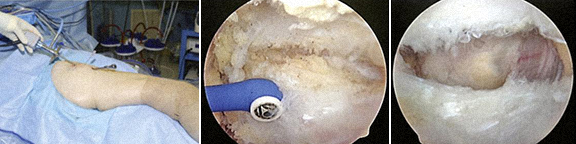

5 - Prótese da anca dolorosa – exérese de tecido fibroso, causa de dor e de mau funcionamento da prótese.